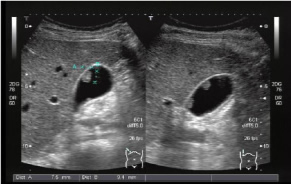

超音波検査とは

超音波検査は、エコー検査とも呼ばれています。お腹の赤ちゃんを見るときと同じ検査です。体の中での音波の反射を利用して臓器の形態や血流などを観察する検査です。耳では聞くことができない高い周波数の音波(超音波)を使用しています。

超音波検査の特徴

・人体には無害です(妊娠中の方でも受けられます)。

・痛みはほとんどありません。

・瞬時に画像をえることができるので正確な判定が可能です。

超音波検査でこんなことが分かります

腹部超音波 脂肪肝、胆嚢ポリープ、胆嚢結石、腎結石、良性(悪性)腫瘍など

甲状腺超音波 甲状腺腫瘍、頸部のリンパ節